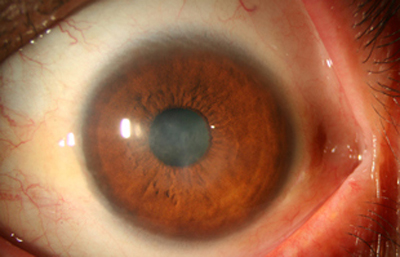

Superficie corneal irregular y grisácea, (Fig. 1, 2) con opácidades granulares en parche y formación de líneas epiteliales elevadas de aspecto granular (Fig. 3), que pueden arborizar dando imágenes de pseudodendritas. Opacidades superficiales satélites. (Figura 4) Inyección ciliar. Ulceración epitelial variante. (Figura 5).

La vascularización y el hipopion son poco frecuentes en los estadios tempranos de la queratitis. Con el tiempo, en los estados avanzados de invasión estromal, aparecen vasos estromales (Figura 17)